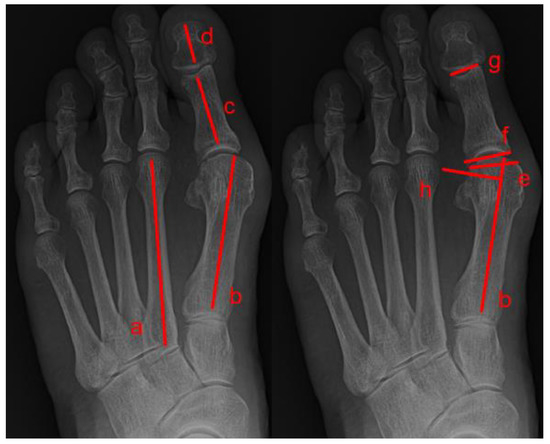

2. Materials and Methods